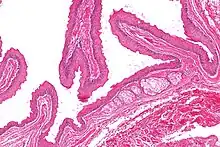

Micrograph of a steatocystoma showing the characteristic corrugated eosinophilic lining. H&E stain | |